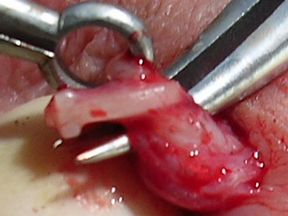

Of the four patients on whom I performed the VasClip procedure in the presence of the founder of the company, two experienced early failure. This 50% early failure rate is not acceptable and I no longer perform the VasClip procedure. The other two patients became sperm-free, but they are aware of the other two early failures and they have been encouraged to have their semen checked periodically for the delayed reappearance of sperm (late failure). The photos below were taken during the repeat vasectomy (on 2/23/05) of a man who had experienced VasClip failure.